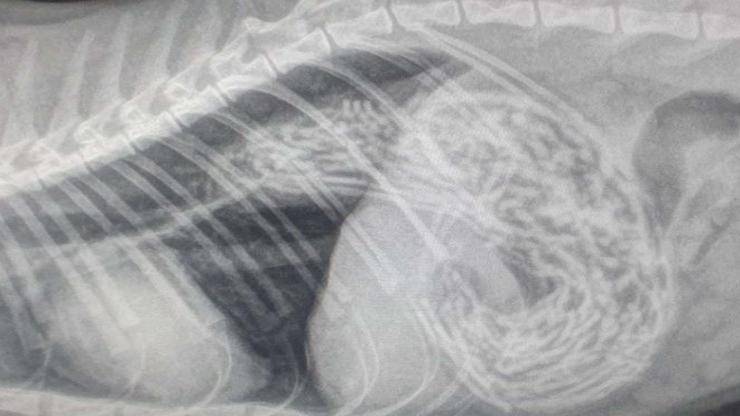

Nessuno dei due si aspettava di fare un ritrovamento del genere svelato dalla radiografia. Tutto è partito da un malessere avvertito dalla gattina di Paul che aveva smesso di mangiare e non aveva lo stesso appetito, quindi il suo strano atteggiamento ha provocato ansia nella sua padrona che è subito corsa ai ripari. Non ci ha pensato due volte e ha portato la sua gatta dal veterinario per farle ricevere le visite di cui aveva bisogno.Una volta giunti lì, il veterinario ha voluto controllare lo stomaco del felino, facendo una scoperta sconcertante. Dalle lastre è emerso che all’interno del suo apparato gastrico c’era un elastico dei capelli incastrato tra l’esofago e lo stomaco. A quel punto, l’unica soluzione da adottare era quella di procedere con l’intervento chirurgico. Questo infatti era l’unico metodo necessario per salvarla.

L’operazione non è stata semplice come si possa pensare perché è durata ben tre ore. I medici hanno dovuto asportare 50 elastici presenti nello stomaco di Berry. Un numero considerevole che nessuno avrebbe mai immaginato. Tuttavia, ciò che conta più di ogni altra cosa è che la piccola stia bene e sia in salute. Riguardo alla brutta vicenda che hanno trascorso, la famiglia di Paul ha riferito di non aver mai pensato al fatto che gli elastici per capelli potessero costituire un pericolo per la vita del loro animale domestico. Purtroppo il triste episodio ha creato dei sensi di colpa nei padroni che non si sono accorti di ciò che aveva ingerito il loro micio. “Ora ha più appetito e siamo convinti che abbia ingoiato questi elastici per molto tempo..forse anche per un anno e mezzo. Nessuno di noi ha mai pensato al rischio che questi oggetti quotidiani potessero avere quotidianamente” hanno riferito il papà e la mamma umana di Berry. Insieme hanno dovuto affrontare una brutta esperienza ma ha reso ancora più saldo il loro legame. Gli incidenti con gli animali domestici sono sempre più frequenti, l’importante è accorgersene in tempo, risolvendoli nel più breve tempo possibile.